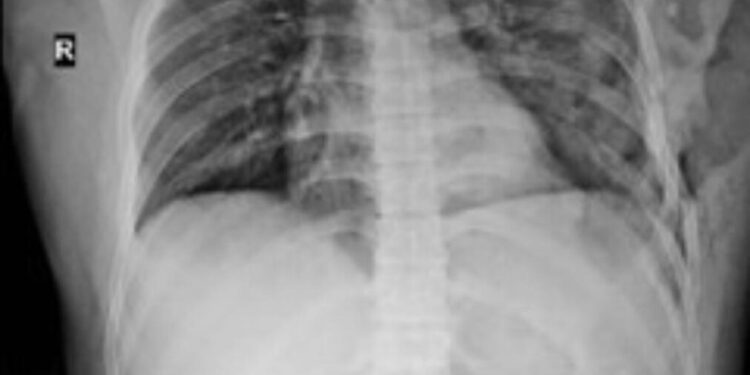

Sau hơn 18 tháng triển khai, các bác sĩ đã thực hiện trên 12 ca bệnh với độ tuổi trung bình từ 24 – 61 tuổi, nam giới chiếm 91,67%. Nguyên nhân chủ yếu là do tai nạn giao thông, trong đó có nhiều chấn thương ngoại khoa thể nặng và rất nặng gồm mảng sườn di động bên chiếm 25%, biến dạng lồng ngực chiếm 75%. Tất cả các trường hợp bệnh nhân đã điều trị đến nay đều ghi nhận hiệu quả rất tốt.

Phẫu thuật kết hợp xương sườn được tiến hành bằng các đường mổ dọc theo xương sườn, bộc lộ ổ gãy xương, và có thể kết hợp với nội soi lồng ngực để nhìn rõ ổ gãy từ bên trong, đồng thời, thám sát khoang màng phổi, kiểm tra các tổn thương tiềm ẩn bên trong, kiểm soát chảy máu trong suốt quá trình mổ, khâu tổn thương nhu mô phổi nếu có, hút bỏ máu tụ, và gây tê thần kinh liên sườn, giúp giảm đau tuyệt vời sau mổ.